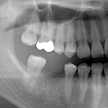

1. 初診時X線パノラマ

平成19年の年末に初めて来院した時のX線パノラマです。主訴が右下6番の銀歯の脱離との事ですが、同部はもう残根となり抜歯必至です。他には上顎親知らず。左上4番の転位歯、左下5番の埋伏と6番の不良根充が目立ちます。